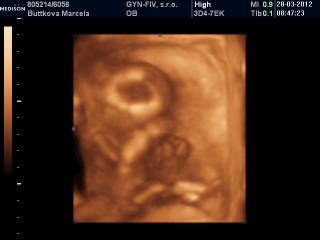

Ahojte,

toto som našla🙂

@marcelatje jééééj.......už aj ja chcem ísť na usg 🙂

@vladka1828 mám aj krajšie fotečky, ale akosi mi tie čísla fotiek v prezentácii nesedia s číslami fotiek na CD tak sem dalo úplne iné ako som chcela 😒 Každopádne to bol zážitok a vrelo každému odporúčam 🙂

@marcelatje nevadí, aj tieto sú pekné 😉 ja by som na to asi pozerala deň-noc 🙂 mne vždy slza vyskočí aj pri normálnom usg, minule keď som videla ako si pekne kopkalo nožkami - taká som bola šťastná 🙂

@marcelatje zlatučké je Tvoje maličké 🙂